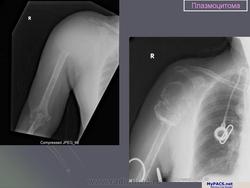

Плазмоцитома.